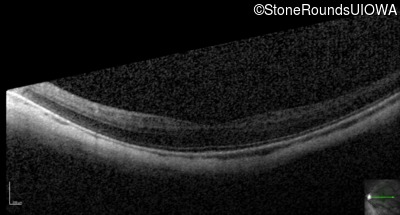

Optical Coherence Tomography - Right - 20/25 -1

Exemplar / OCT Stack

OCT Stack